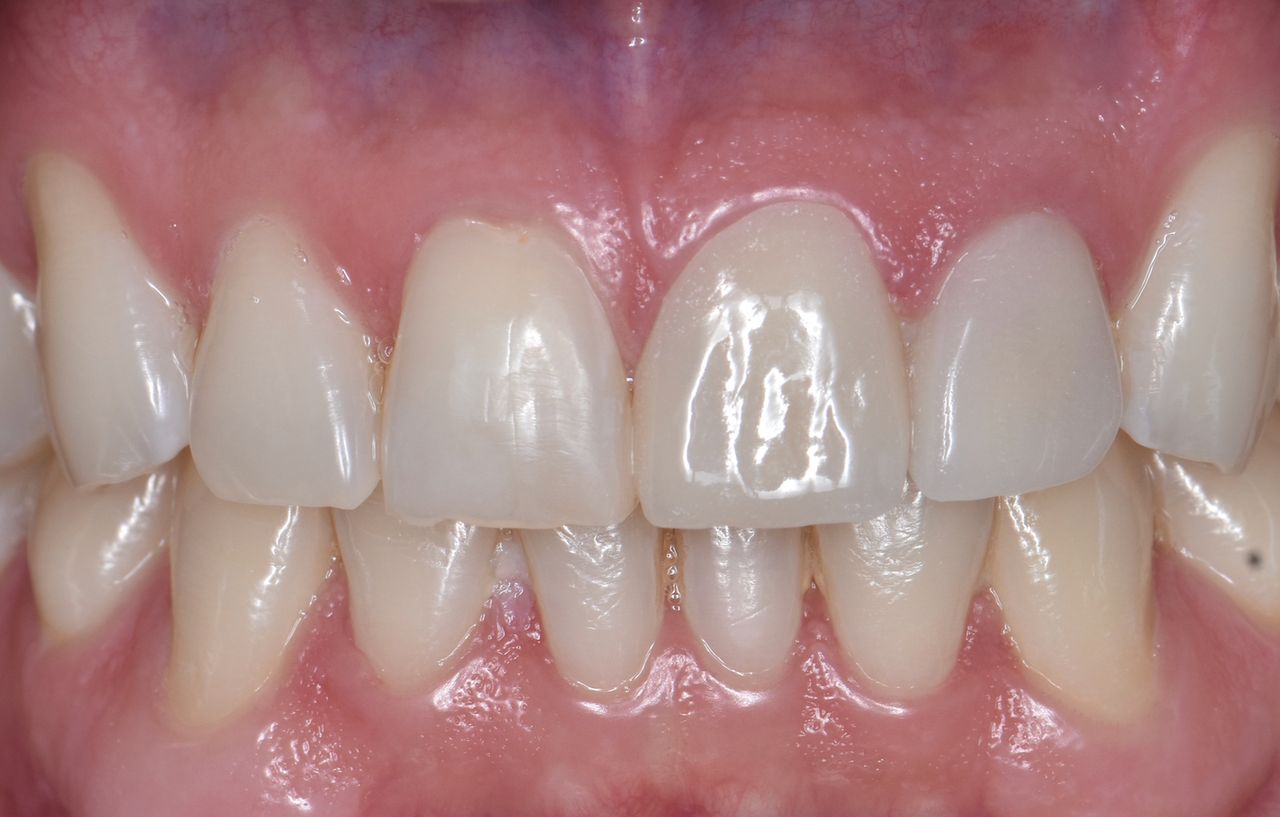

Traumatismo dental

PROMOCIÓN, 50% DE DESCUENTO EN TU SEGUNDO IMPLANTE

Implante dental

Los implantes dentales son la forma mas estética y funcional de sustituir una diente perdido, ya sea por caries, enfermedad periodontal, traumatismo o agenesia. Lo mas importante para que este tratamiento sea exitoso es su correcta planeación.